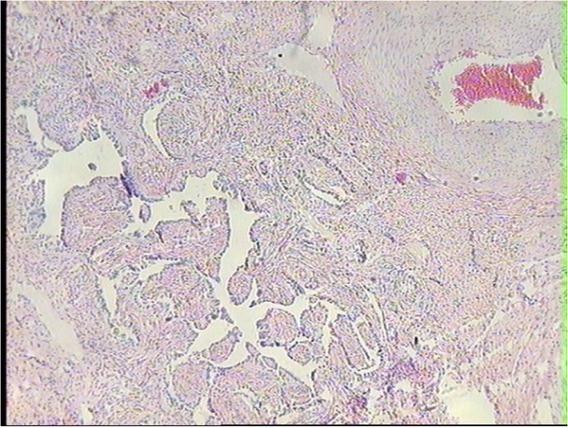

Uterus histopathological changes. In all examined uterus specimens, pathological changes characteristic of the adenomyosis disease process were diagnosed. They were the proliferation of basal mucosal glands, and mucosa interstitial tissue, atrophy of glands of the superficial mucosa layer, and small foci of inflammatory cell infiltration in the mucosa layer (Figs 1, 2, 3). Among the examined cows, these types of pathological changes were found to highly varying degrees.

Foci of the endometrial pathological tissue disseminated in the muscular layer in the uterus of dairy cow. HE, 10×